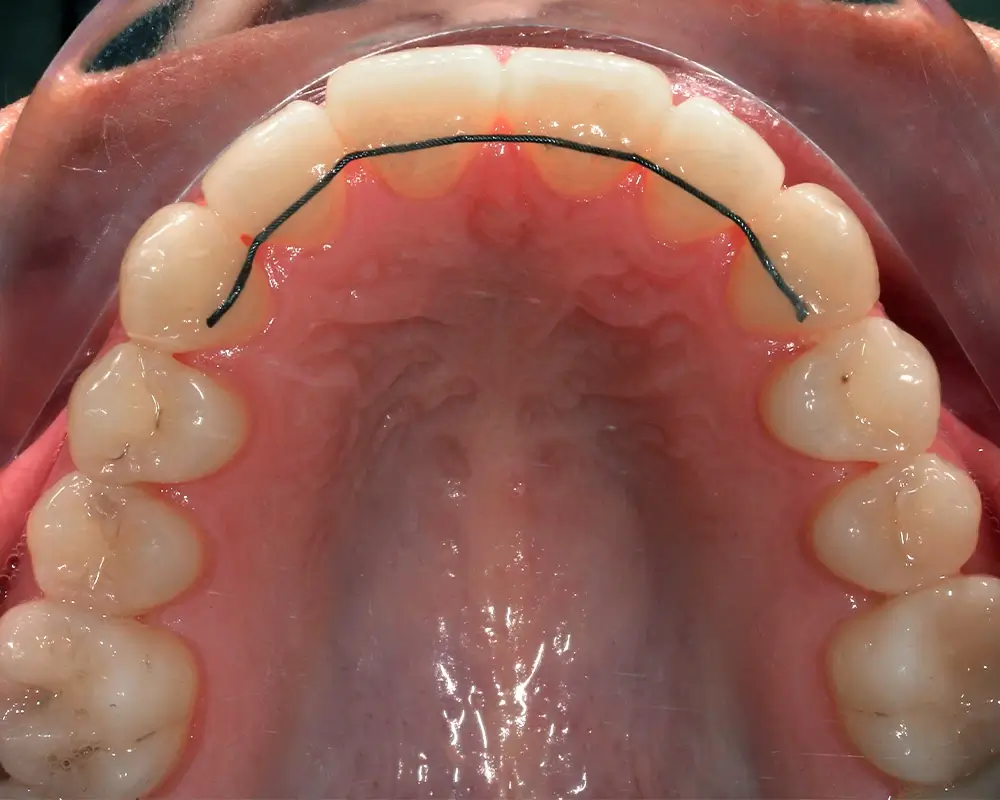

Открытый прикус - Кейс 6

Эффективность устранения дефекта прикуса посредством элайнеров FlexiLigner.

Результаты лечения